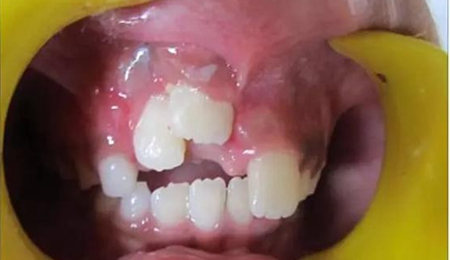

健康的 7 歲男童,前一天摔倒,上頜右中切牙和右側(cè)切牙發(fā)生挫入脫位(圖 1)。無牙外傷史,無神經(jīng)并發(fā)癥病史。檢查發(fā)現(xiàn)雙側(cè)下頜下腺增大。

(圖1)

口腔內(nèi)發(fā)現(xiàn):混合牙列早期,覆蓋正常,安氏I類磨牙關(guān)系。牙11和12齦緣紅腫。

牙11,12 和21對(duì)叩診敏感。牙11嚴(yán)重挫入(牙11和牙12的切緣相差7毫米),并挫入牙槽窩。與牙21相比,牙12大約挫入4毫米。